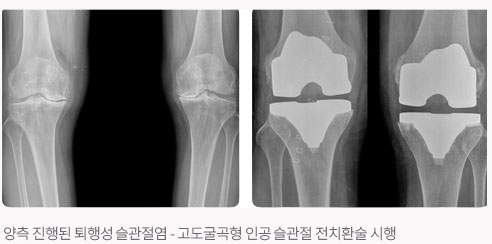

본원에서는 최신의 수술 기법과 인공 관절 기구(최소 절개 수술법, 대형 세라믹 대퇴 골두 치환술, 고도굴곡형 인공 슬관절 치환술)를 사용하여 연간 200명 이상의 환자들에게 통증없는 생활로의 전환을 도와드리고 있습니다.

인공 슬관절 치환술이란?

인공 고관절 전치환술이 발달하고 결과가 좋아지면서 자연히 관절 마모가 심한 슬관절에도 인공 관절 치환술이 시행되어져 현재 많은 성공적인 디자인으로 좋은 결과를 보이고 있습니다.

인공 슬관절 전치환술은 슬관절 통증이 일상 생활을 할 수 없을 정도로 심하거나 통증 때문에 보조 기구를 사용해야 걸을 수 있는 사람, 슬관절 통증이 휴식과 상관없이 종일 지속되는 사람, 휴식을 취하거나 약을 복용해도 만성적인 염증이나 부종이 거의 감소되지 않는 사람, 무릎이 안쪽 또는 바깥쪽으로 구부러져 변형이 심한 사람, 무릎이 뻣뻣하고 무릎을 구부리거나 완전히 펴기 힘든 사람에게서 초기에는 통증 감소에 효과가 있던 비스테로이드성 약물(이부프로펜, 아스피린 등)이 이제는 더 이상 효과가 없는 사람, 진통제를 먹으면 위장장애가 너무 심하고 합병증으로 생활하기 힘든 사람들에게서 물리치료와 같은 다른 치료 요법이 효과가 없을 때 수술을 시행합니다. 인공 슬관절 치환술을 받은 환자들의 90%이상이 먼저 현저한 통증 감소와 변형의 교정 그리고 힘들었던 일상생활이 보다 편안하고 자유로와짐을 느낍니다. 산책, 수영, 골프, 운전, 가벼운 등산, 가벼운 자전거 타기 등의 활동을 거의 통증 없이 수행할 수 있습니다. 인공 관절의 특징으로 환자는 수술 상처 부위의 피부 감각이 다소 무뎌졌음을 느낄 수 있습니다. 또한 과도하게 관절을 구부릴 때에 약간 뻣뻣한 감을 느낄 수도 있고, 무릎을 완전히 꿇는 것은 불편하지만 점차 가능해집니다. 때때로 무릎을 구부리거나 펼 때 금속과 플라스틱이 부딪히는 소리가 날 수도 있으나 시간이 지날수록 감소되며, 수술 전에 겪었던 통증이나 기능 장애에 비하면 조그마한 문제에 지나지 않습니다. 수술 후 규칙적으로 가벼운 운동 프로그램에 반드시 참가하여, 근력을 강화시키고 인공 관절이 신체에 잘 적응되도록하고 낙상과 상해 방지를 위해 각별히 조심해야 합니다. 치아 검진을 받을 때 반드시 인공 관절 수술한 것을 말해주어야 사전에 항생제를 복용하여 예상되는 감염을 막을 수 있습니다. 정기적으로 병원을 방문하여 정형 외과 의사의 검진을 받아야 합니다. 대개 60세 이상의 나이에 X-선상에서 연골이 완전히 닳아 없어져 뼈와 뼈끼리 부딪히는 상태에서는 거의 통증이 약으로는 조절이 안되며 걸을 때 심하게 아프다고 호소합니다. 이런 경우에 인공 슬관절 치환술을 시행하여 휜다리를 바로 잡아주고 마모된 연골을 인공 대치물로 바꾸어 주면 통증이 사라지고 정상적인 보행을 가능하게 하여 줍니다. 무릎 인공 관절의 수명은 과거에는 5~10년 정도 후에 반드시 재수술을 해야 한다고 했으나, 현재는 그보다 더 오랜기간까지도 사용이 가능한 것으로 알려져 있으며, 인공 관절의 수명 때문에 수술을 꺼릴 필요는 없다고 봅니다. 수술 후 다음날(한쪽 다리만 수술했을 경우) 무릎을 굽혔다 폈다 할 수 있도록 만들어진 기계를 통해 환자 스스로 움직이는 연습을 시작할 수 있습니다. 양쪽 다리를 모두 수술한 경우에는 수술 후 이틀째부터 시작합니다. 걷는 연습은 한쪽다리의 경우 2~3일째부터, 양쪽 다리는 5~7일째부터 연습을 시작합니다. 퇴원은 한쪽다리의 경우는 수술 후 2주, 양쪽 다리의 경우는 3~4주경 입니다. 퇴원 시에는 목발이 없이도 정상인과 비슷한 보행을 할 수 있게 됩니다. 수술 후 3개월까지는 병원에서 준 약을 복용해야합니다. 퇴원 후 대게 1~2개월까지는 붓고 열감이 있으므로, 붓기를 가라앉히기 위한 얼음 찜질을 하고, 물리치료도 좋지만 순환을 위해 자주 목욕탕에 가는 것이 좋습니다. 목욕 후에는 역시 얼음 찜질을 해야 합니다. 붓기가 가라앉고 열감이 없으면 온찜질을 하고, 술은 3개월까지 삼가하고 미끄러지거나 넘어지지 않도록 주의 해야합니다.